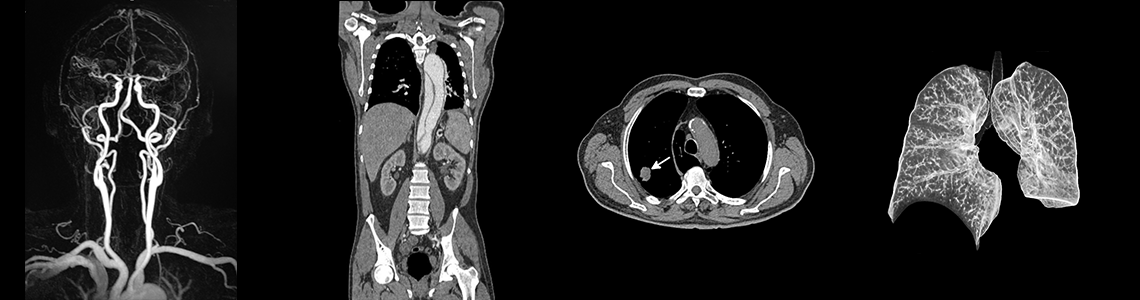

Magnetresonanztomographie (MRT), Computertomographie (CT)

Schnittbildverfahren in Röntgentechnik. Organe des Abdomens und Beckens. Thoraxorgane mit Herz, Lungen und Gefäße. Angiographie, Gefäßdarstellung. Kopf, Schädelbasis, Verkalkungen, Hydrocephalus, Raumforderungen der Halsweichteile und der Nasennebenhöhlen, Verlaufsbeobachtungen der Onkologie, Hämatologie und Erkrankungen des lymphatischen Systems. Skelettsystem, Gelenke, Wirbelsäule, Frakturen, Muskelerkrankungen, Tumorerkrankungen, Metastasen, Blutungen, Schlaganfall, Retroperitoneum mit Nieren, Harnblase, Urogramm, Organe des kleinen Beckens, wie Prostata, Uterus, Ovarien, Adnexen.